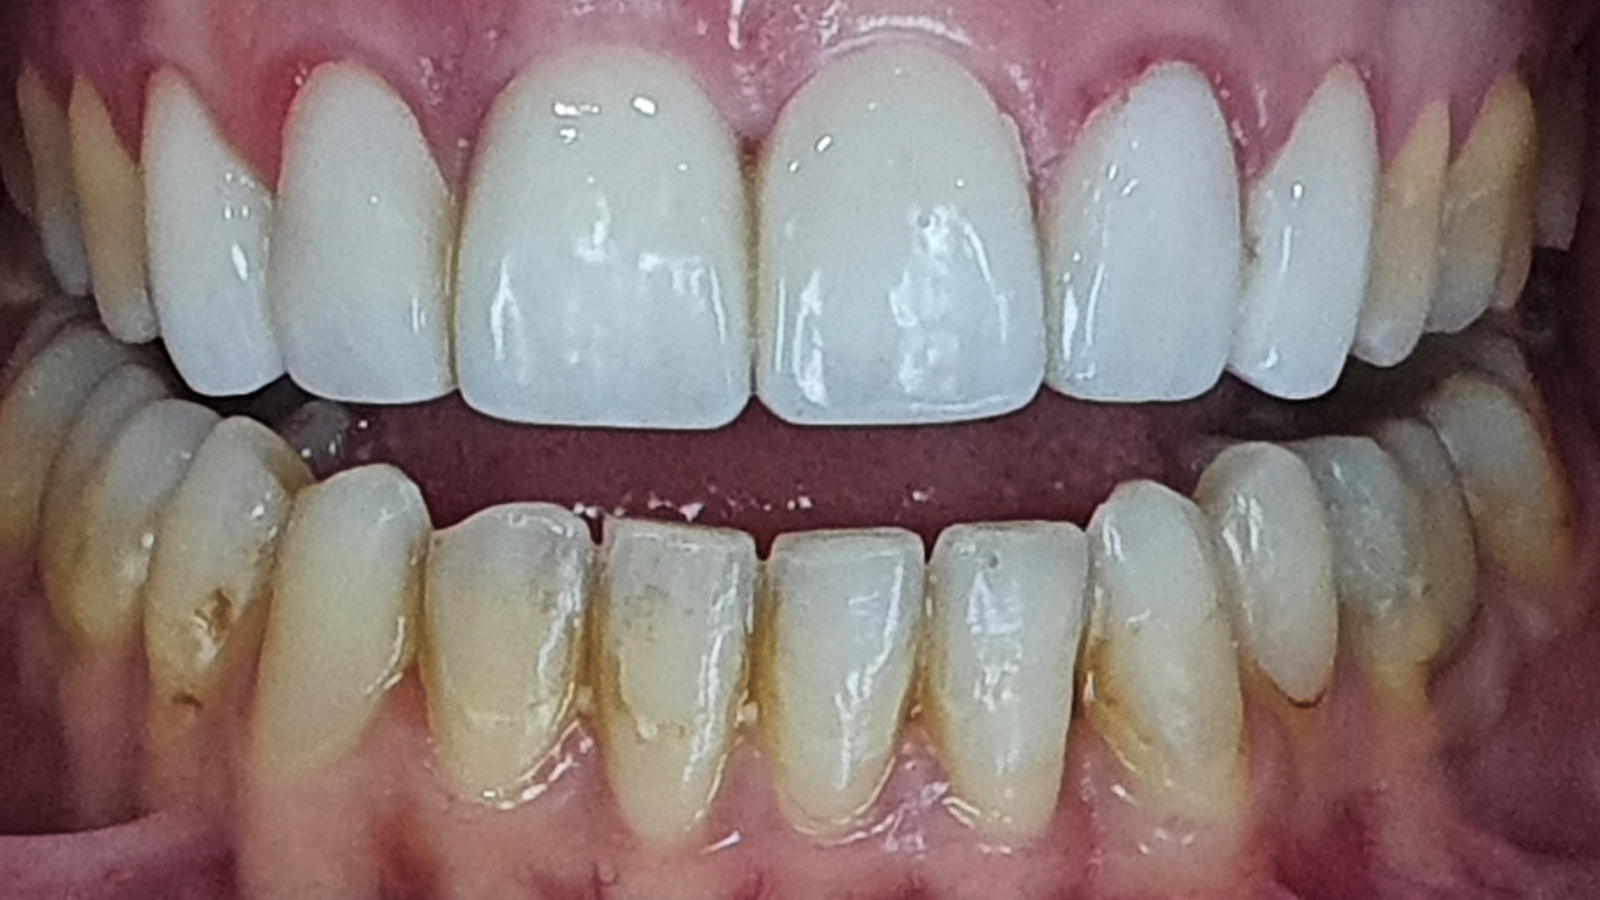

Remplacement de facettes : plus d’harmonie, de translucidité et respect gingival

Une jeune patiente se présente avec des facettes peu esthétiques, opaques et à la forme carrée.

Elles ont été remplacées par de nouvelles facettes aux formes plus harmonieuses, avec davantage de translucidité et surtout une meilleure intégration au niveau de la gencive.

Les images “Après” mettent en évidence un sourire plus naturel, plus lumineux, et une transition plus douce entre la dent et la gencive.

Images :